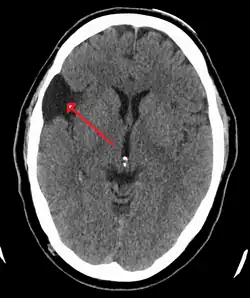

A CT scan of an arachnoid cyst

CT scan of a colloid cyst

The diagnostic process typically begins with a medical history workup followed by a medical examination by a physician. Imaging tests, such as CT scans and MRIs, help provide a clearer picture. The physician typically looks for fluid (or other bodily substance) filled sacs to appear in the scans, as is shown in the CT scan of a colloid cyst. A primary health care provider will refer an individual to a neurologist or neurosurgeon for further examination. Other diagnostic methods include radiological examinations and macroscopic examinations. After a diagnosis has been made, immunohistochemistry may be used to differentiate between epithelial cysts and arachnoid cysts.[2] These examinations are useful to get a general idea of possible treatment options, but can be unsatisfactory to diagnose CNS cysts.[3][5] Professionals still do not fully understand how cysts form; however, analyzing the walls of different cyst types, using electron microscopes and light microscopes, has proven to be the best diagnostic tool. This has led to more accurate cyst classification and correct course of action for treatments that are cyst specific. In the past, before imaging scans or tests were available, medical professionals could only diagnose cysts via exploratory surgery.[2]